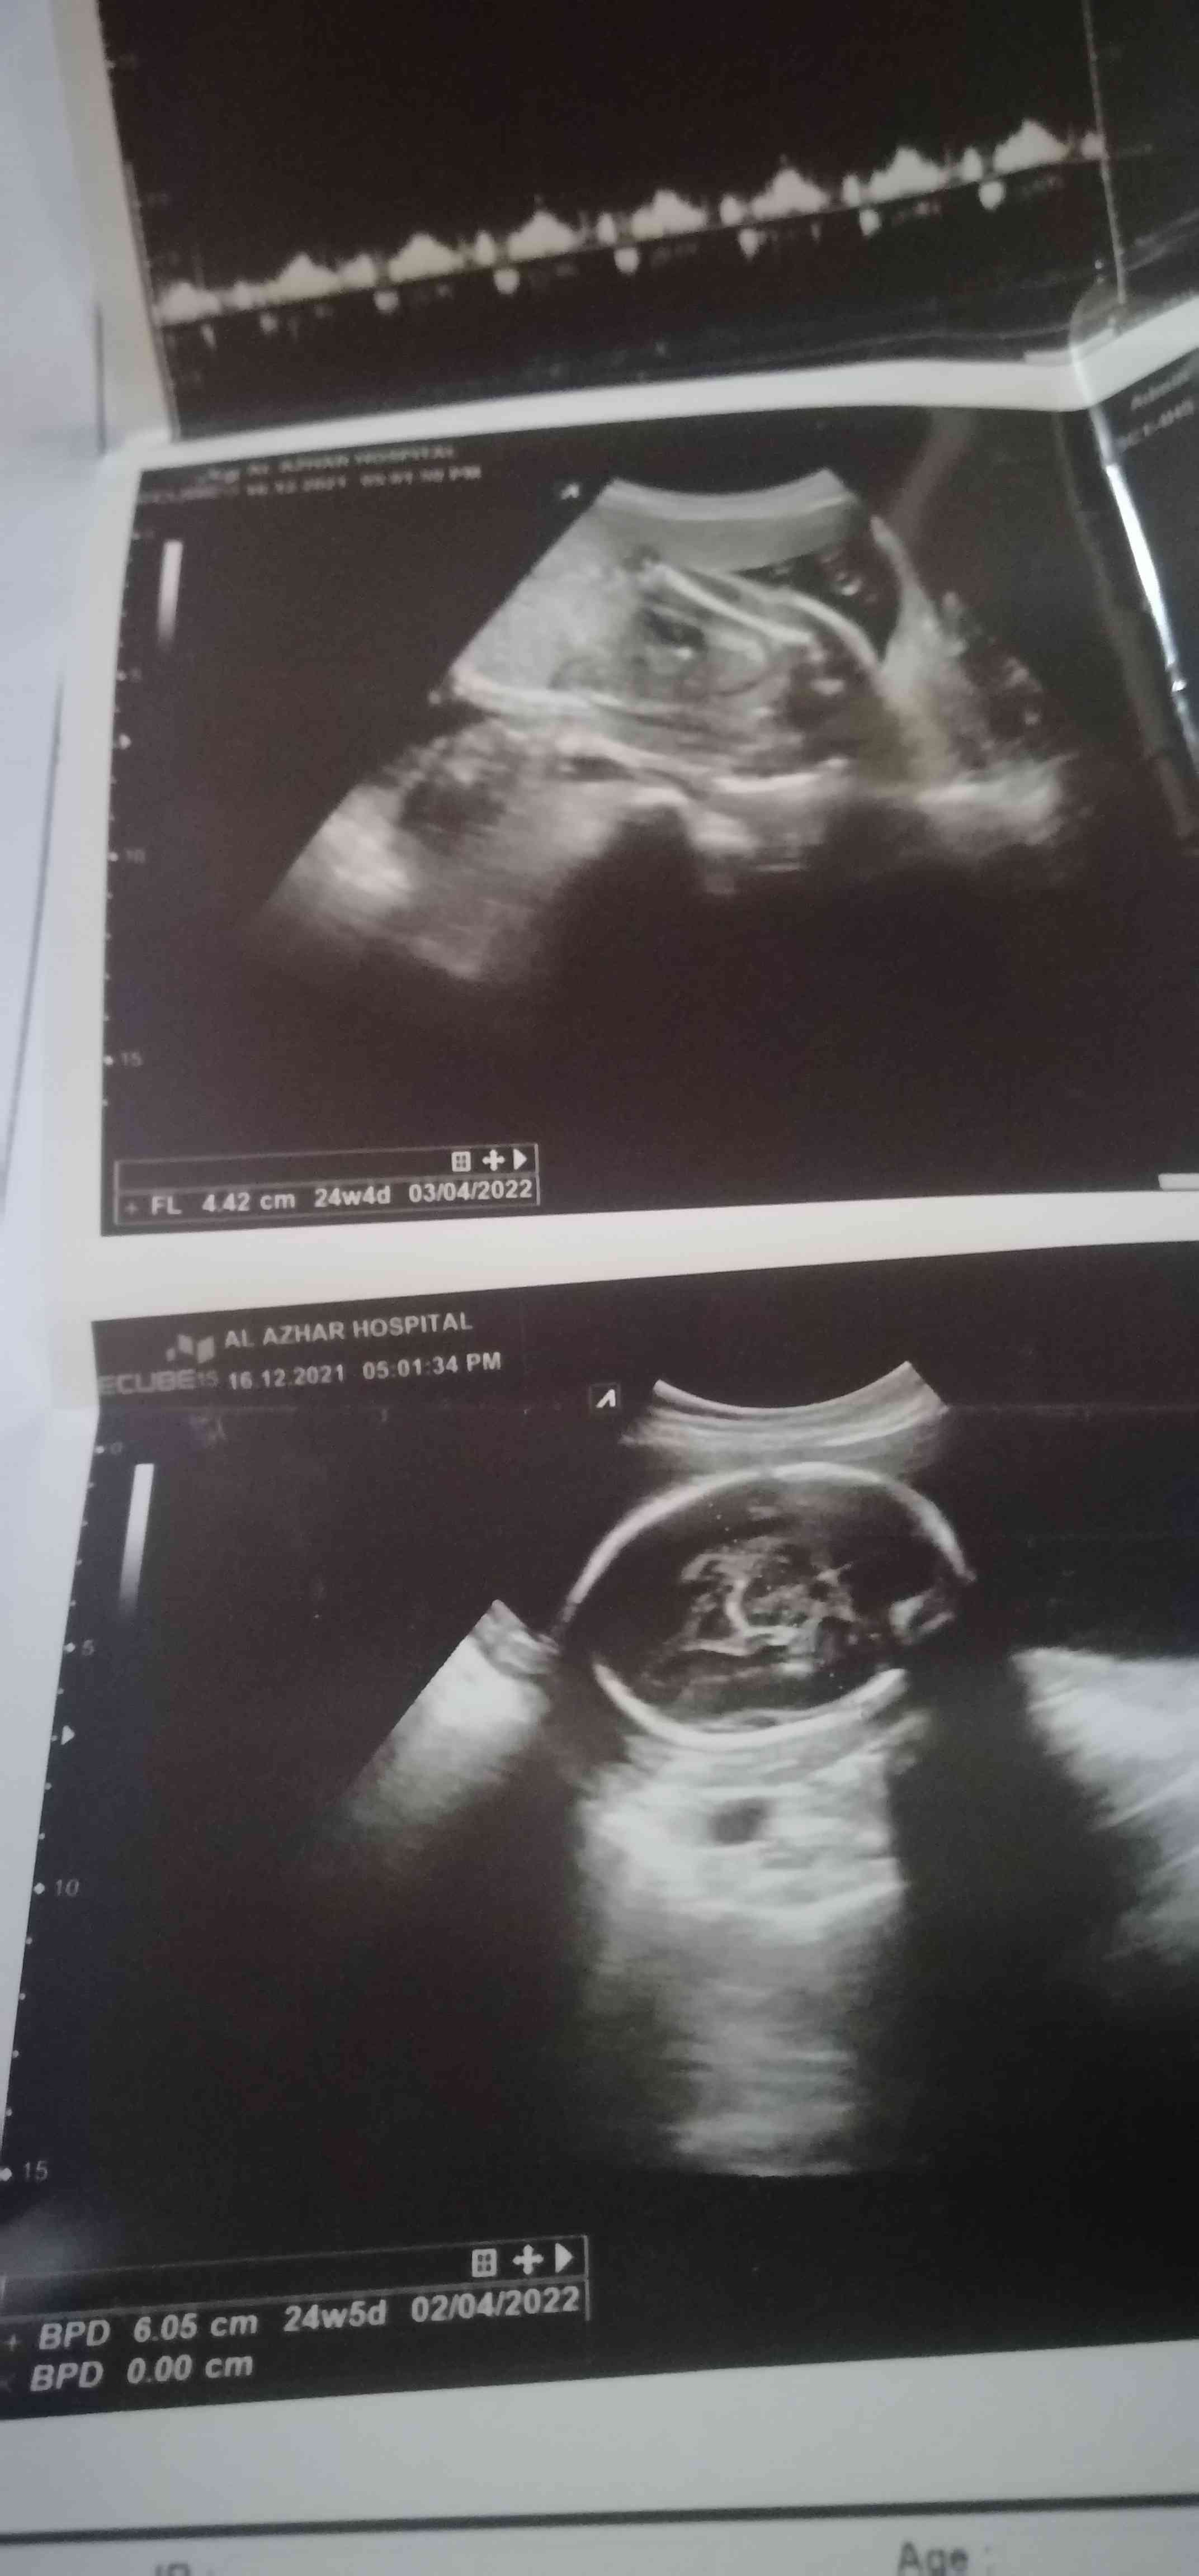

اتمنى افادتي بالتقرير،... ماهو مكتوب واتمنى استشارتكم بما افعل حيال هذا الامر ولكم جزيل الشكر

حامل في الأسبوع 24 و 3 ايام وزن الجنين 714 والقياسات الأخرى gr Bpd 5.81cm / Fl 4.30 cm هل...